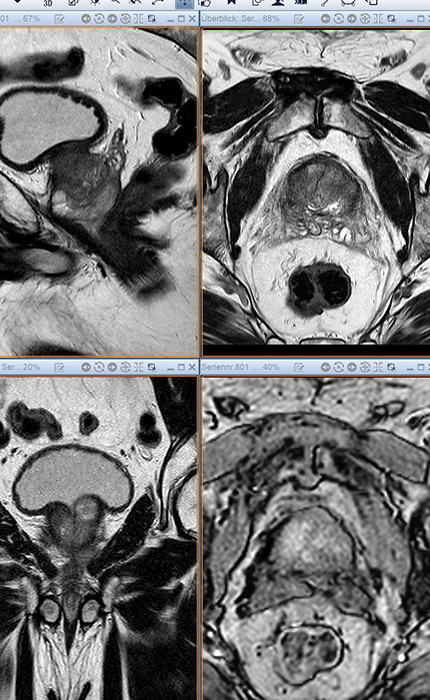

Prostata

Vorsteherdrüse

Die Prostata oder Vorsteherdrüse liegt beim Mann unterhalb der Harnblase und umschließt dort ringförmig den Anfangsteil der Harnröhre (Uretra) bis zum Beckenboden. An die Rückseite der Prostata grenzt der Enddarm (Rektum). Ab dem 50. Lebensjahr treten bei fast jedem zweiten Mann Veränderungen der Prostata auf. Am häufigsten kommt es zu einer gutartigen Vergrößerung der Prostata, einer sogenannten benignen Prostatahyperplasie. Diese hat ihren Ausgangspunkt in dem Teil der Prostata, welcher direkt der Harnröhre anliegt. Dadurch kann es zu einer Einengung der Harnröhre kommen, was einen schwächer werdenden Harnstrahl und einen häufigeren Harndrang bedingt. Neben gutartigen Veränderungen der Prostata kann es aber auch zu einem Prostatakrebs (Prostatakarzinom) kommen. Ein Prostatakarzinom entsteht in der Mehrzahl der Fälle in der äußeren Zone, welche nicht unmittelbar der Harnröhre anliegt. Da ein Prostatakarzinom meistens sehr lange keine Beschwerden verursacht, wird es oft nicht frühzeitig gefunden. Allerdings gilt: Je früher es festgestellt wird, desto besser sind die Chancen für eine vollständige Heilung.

Prostatakrebs ist mit ca. 23 % die häufigste Krebserkrankung von Männern in Deutschland und jährlich werden über 60.000 neue Prostatakrebsfälle diagnostiziert. Prostatakrebs vor dem 50. Lebensjahr ist selten und die meisten Neuerkrankungen treten ab ca. dem 70. Lebensjahr auf.  Zwar tritt Prostatakrebs häufig auf, aber er ist nicht die am häufigsten zum Tode führende Krebserkrankung. Hier steht der Lungenkrebs weiterhin an erster Stelle. Ungefähr 9 von 10 Männern mit diagnostiziertem Prostatakrebs sterben nicht an diesem Krebs, sondern an einer anderen Ursache. Viele Männer wissen auch nichts von ihrer Erkrankung. Warum ein Prostatakarzinom entsteht ist auch heute noch weitgehend unbekannt. Man kennt allerdings bestimmte Faktoren, die das Risiko einer Prostatakrebserkrankung erhöhen. Neben dem Alter gibt es auch eine familiäre Veranlagung und es spielen Umwelteinflüsse, wie beispielsweise die Ernährung, Lebens- und möglicherweise auch Arbeitsbedingungen eine Rolle.

Männer ab 45 Jahren können einmal jährlich die kostenlosen Leistungen des gesetzlichen Früherkennungsprogramms in Anspruch nehmen, welche neben einem Gespräch, der Untersuchung der Geschlechtsorgane und der Lymphknoten in der Leiste, sowie das Abtasten der Prostata vom Enddarm aus umfasst. Mit dieser Untersuchung können jedoch nur oberflächlich gelegene und größere Karzinome gefunden werden. Die Bestimmung des prostataspezifische Antigen, kurz PSA, im Blut ist nicht Bestandteil des gesetzlichen Früherkennungsprogrammes. PSA wird in der Prostata produziert, ist aber nicht spezifisch für Prostatakrebs. Je höher der Wert, umso wahrscheinlicher ist zwar, dass ein Tumor vorhanden ist, allerdings gibt es diverse, gutartige Faktoren, welche den PSA Wert erhöhen können (z. B. Prostataentzündungen, gutartige Veränderungen, Druck auf die Prostata, etc.). Umgekehrt bedeutet dies leider auch, dass ein normaler PSA-Wert keine Garantie dafür ist, dass kein Krebs vorliegt.

Die Gemeinschaftspraxis bietet ein breites Spektrum von radiologischen und nuklearmedizinischen Untersuchungsverfahren an, welche von der Detektion eines Prostatakarzinoms (multiparametrische Magentresonanztomographie), über die Ausbreitungsdiagnostik bei einem diagnostizierten Prostatakarzinom (Computertomographie, Magnetresonanztomographie, Röntgen) bis zur Ausbreitungs- und Rezidivdiagnostik mittels Knochenszintigraphie und PSMA-PET-CT reichen. Auch bei Schmerzen durch ein in die Knochen metastasiertes, fortgeschrittenes Prostatakarzinom können wir Ihnen mittels Schmerztherapie helfen.